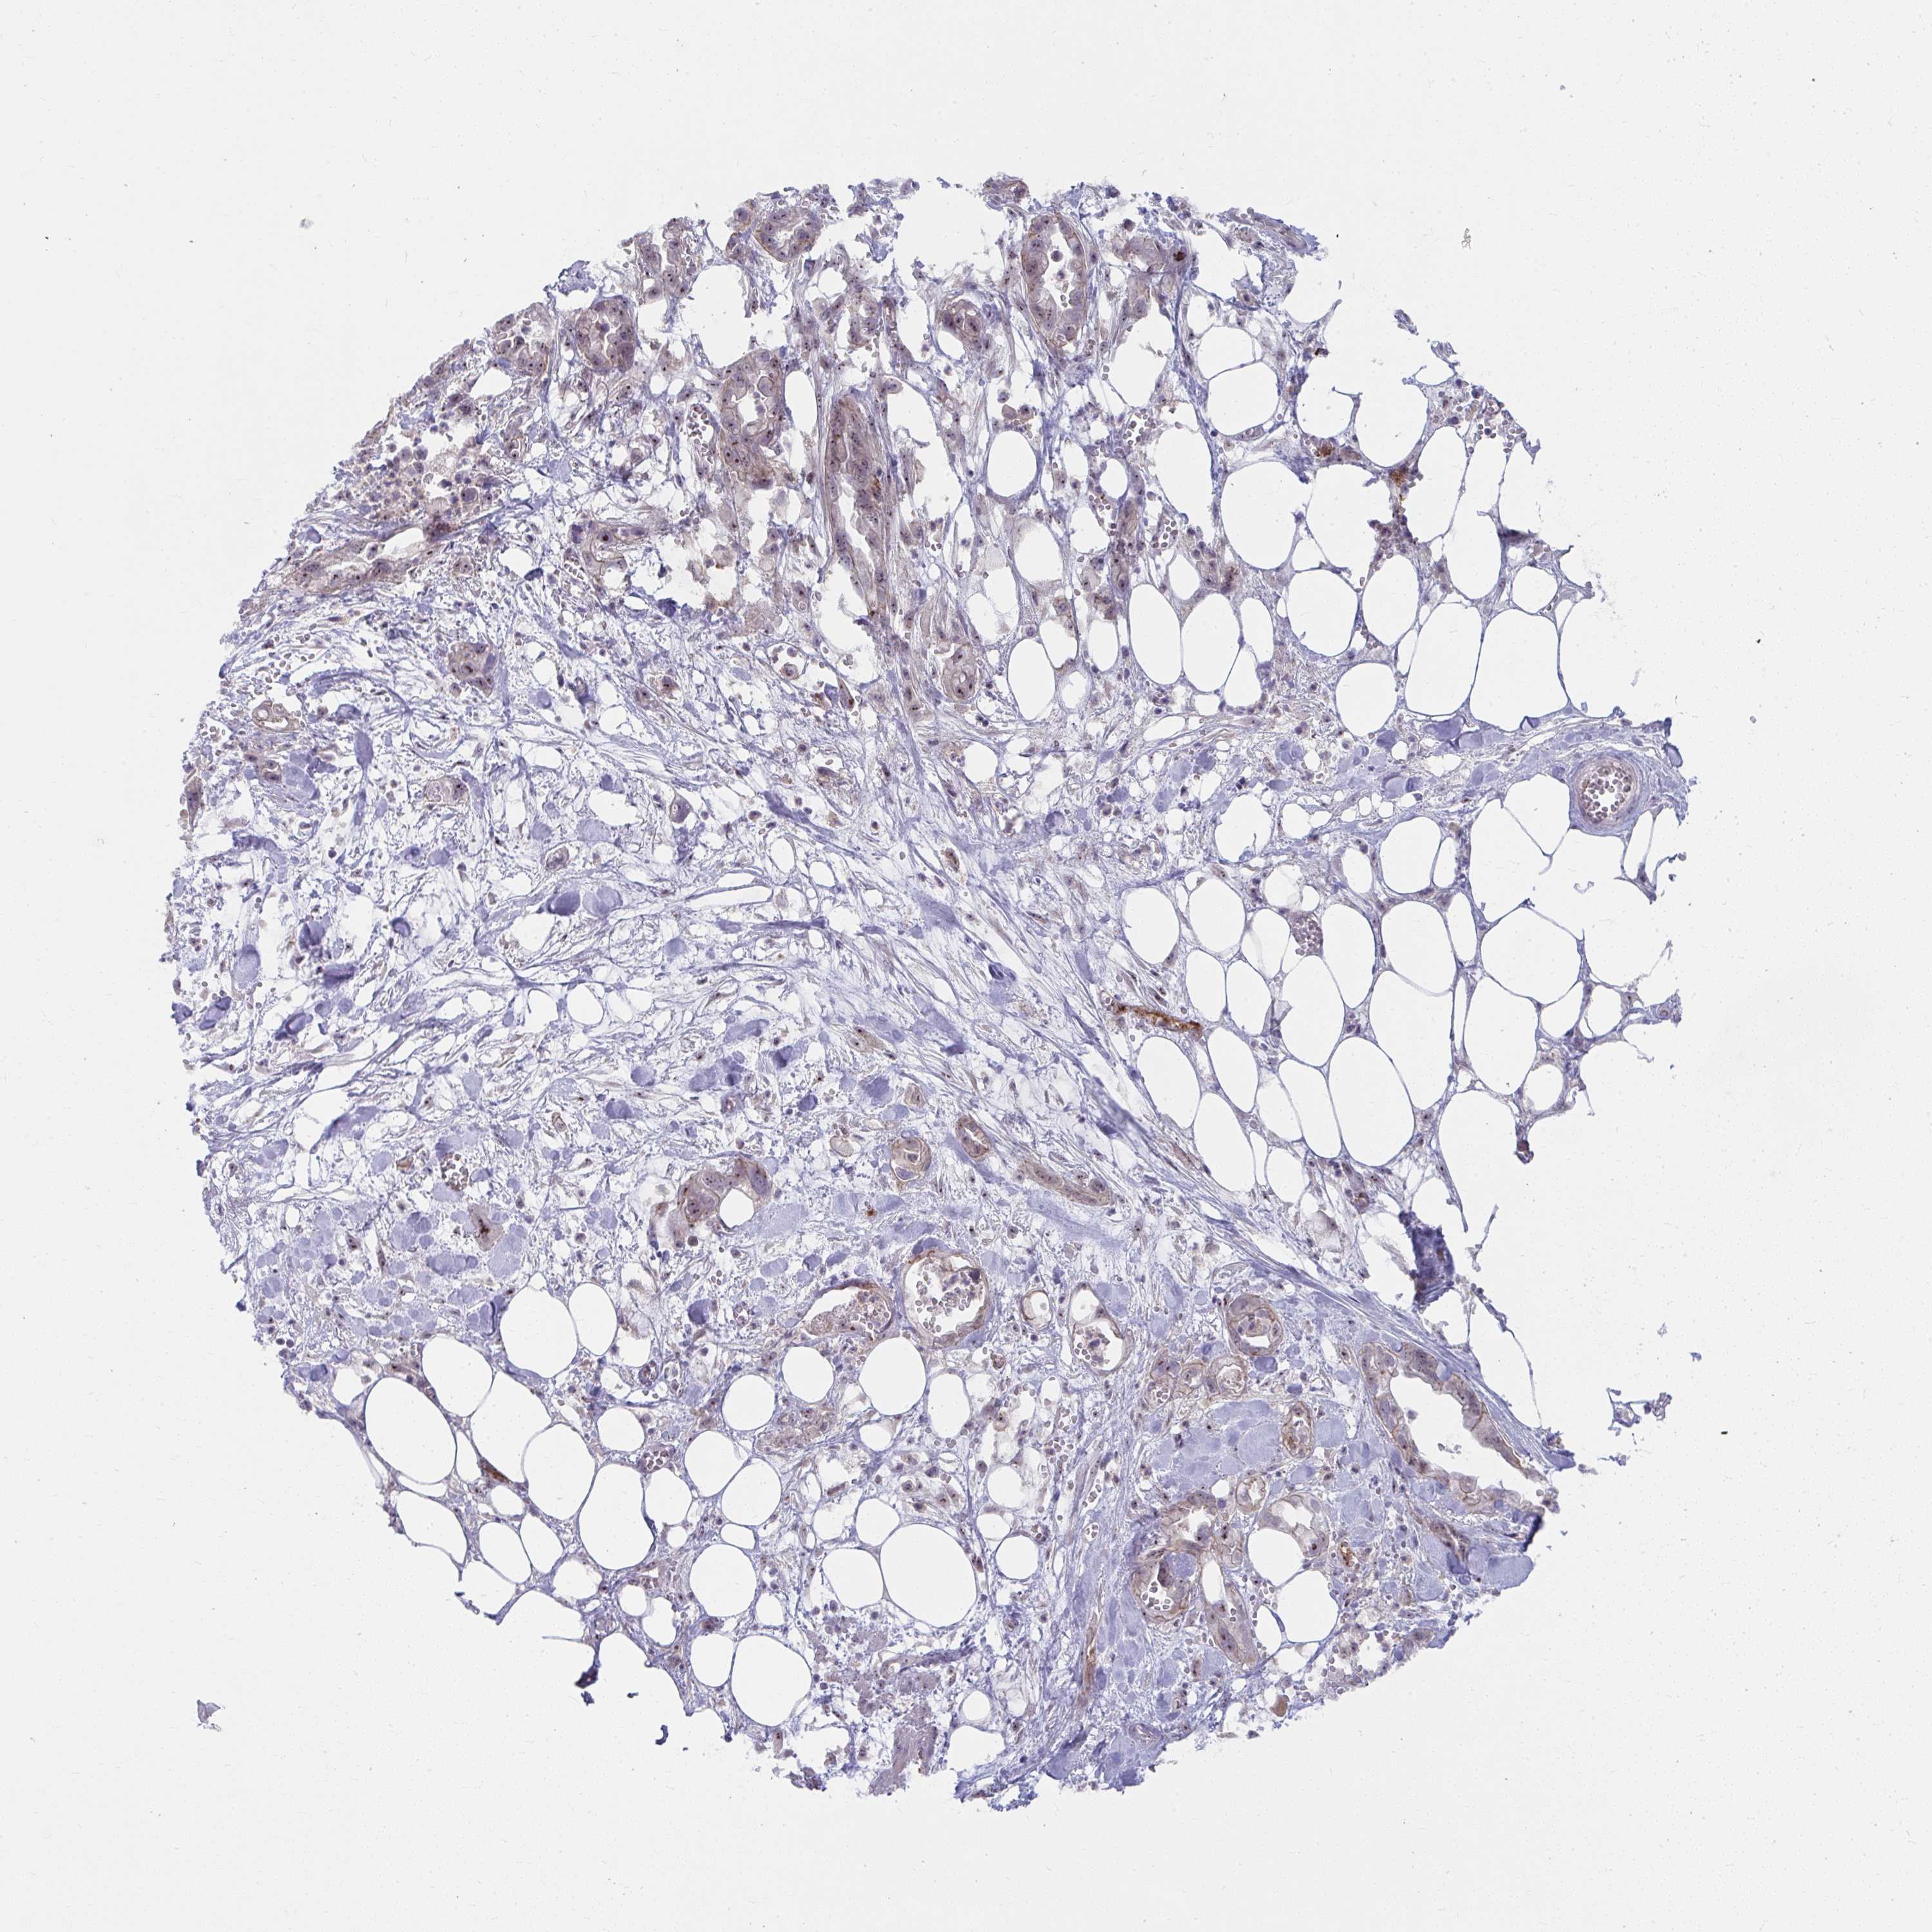

PANCREATIC CANCER - Protein expressioni

A mouse-over function shows sample information and annotation data. Click on an image to view it in a full screen mode. Samples can be filtered based on level of antibody staining by selecting one or several of the following categories: high, medium, low and not detected. The assay and annotation is described here.

Note that samples used for immunohistochemistry by the Human Protein Atlas do not correspond to samples in the TCGA dataset.

Antibody stainingi

Antibody staining in the annotated cell types in the current human tissue is reported as not detected, low, medium, or high, based on conventional immunohistochemistry profiling in selected tissues. This score is based on the combination of the staining intensity and fraction of stained cells.

Each image is clickable and will lead to virtual microscopy that enables deeper exploration of all samples and also displays staining intensity scores, fraction scores and subcellular localization as well as patient and tissue information for each sample.

Antibody HPA059530

Staining

High

Medium

Low

Not detected

Intensity

Strong

Moderate

Weak

Negative

Quantity

>75%

75%-25%

<25%

None

Location

Nuclear

Cytoplasmic/membranous

Cytoplasmic/membranous,nuclear

Adenocarcinoma, NOS